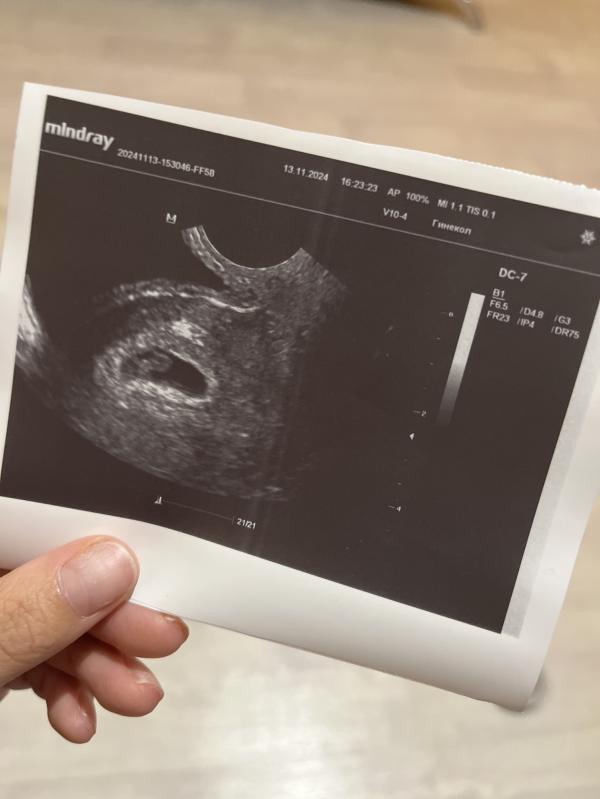

Крошечка сегодня сердечко слушала твое: что это значит и как это понимать?

крошечка🥺🫶🏻сегодня сердечко слушала твое..